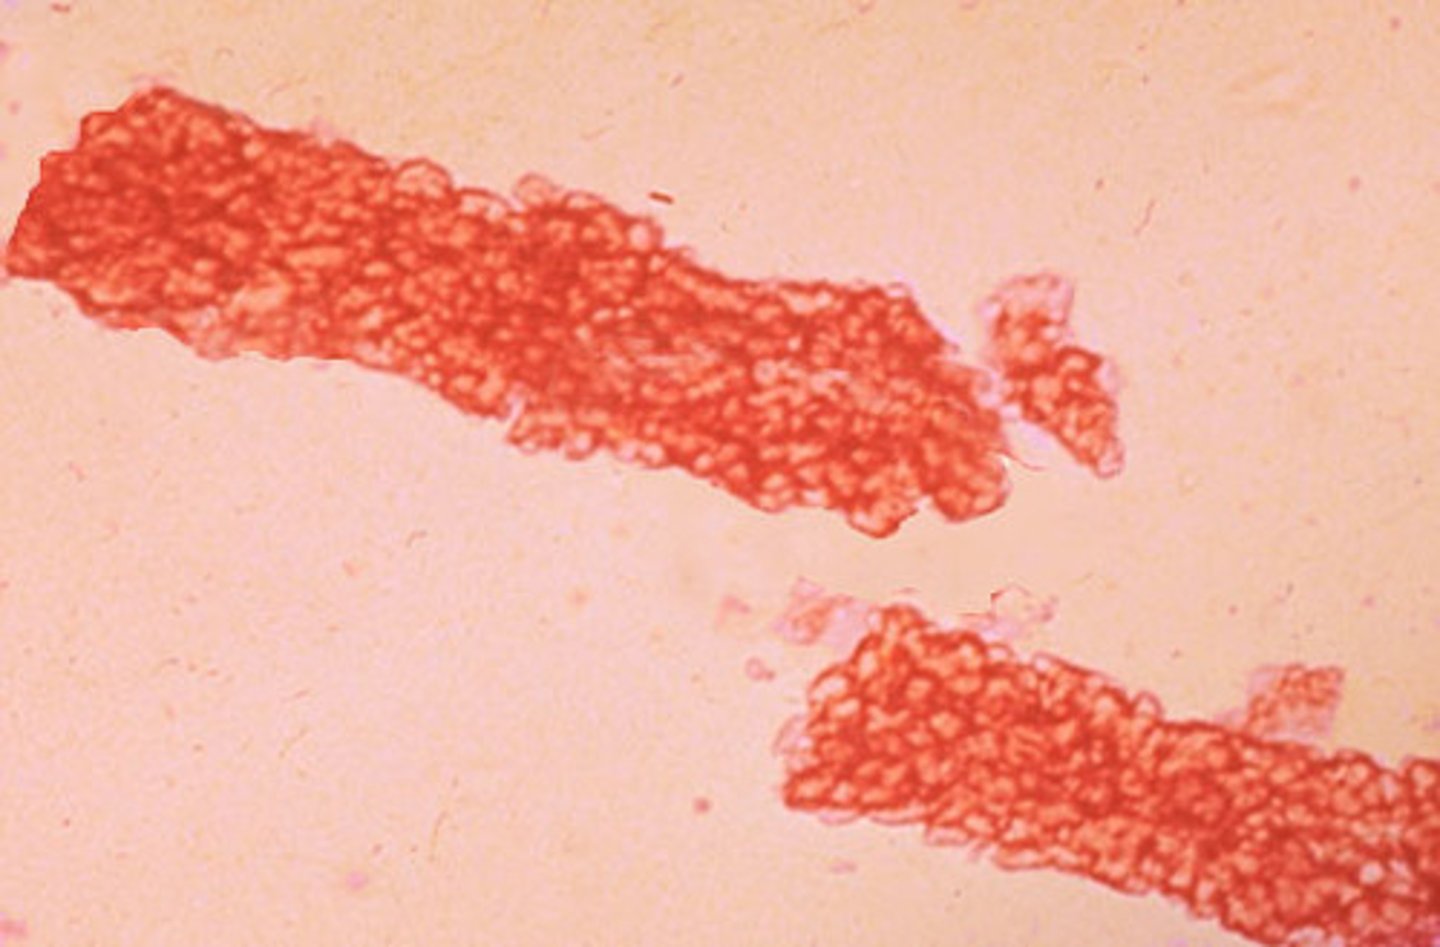

agglutination

unorganized 3D clumping of RBCs